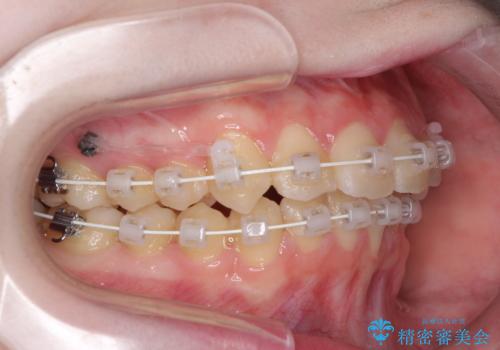

- 矯正装置

- 審美装置

インビザラインでの自己管理は難しいとのことで、ワイヤー装置にて矯正を行うこととしました。